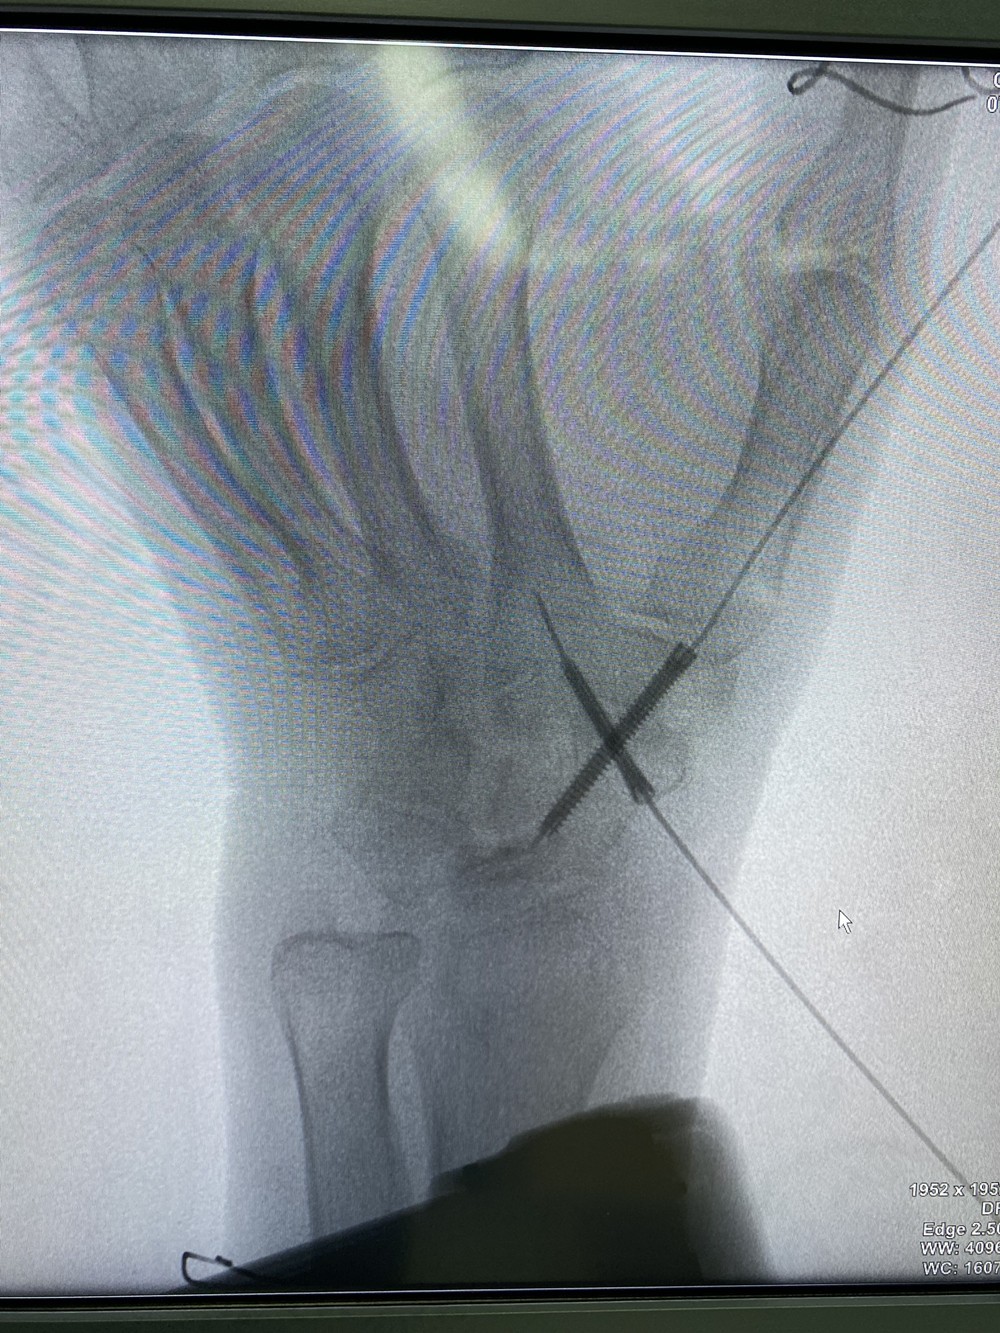

手足显微外科B区郝增涛教授团队成功完成自治区首例“天玑”Ⅱ骨科手术机器人辅助下经皮空心螺钉大小多角骨、舟骨融合术(STT融合)治疗IIIb期月骨无菌性坏死手术。手术十分顺利,固定效果满意,患者恢复良好。这是91直播

完成的首例也是自治区首例“天玑”Ⅱ骨科机器人辅助腕关节疾患手术,标志着91直播

腕部骨病、骨折的智能、精准、微创治疗达到了一个新的高度。

手腕部骨折、骨病目前是手外科领域新的热点和难点,腕骨的不规则性和关节的复杂性决定了手术难度高。常规的手术方式难以做到精准定位,术中经过C臂环扫后得到患者腕关节三维图像信息,经计算机模拟设计出最佳置钉方案,由机械臂精准引导植入各螺钉。真正做到了精准、微创治疗。

机器人引导下的手术能减少螺钉位置的调整,避免损伤毗邻重要的神经血管组织,提高手术的精确度,减少手术并发症,缩短手术时间。骨科机器人的临床应用使手外科的手术越来越智能化、精准化。机器人在腕关节尤其是舟骨骨折等骨折的治疗上体现出了极大的优越性,极大地提高了手术的精准度,最大程度地减少了手术创伤,术后患者能更快更好的恢复。